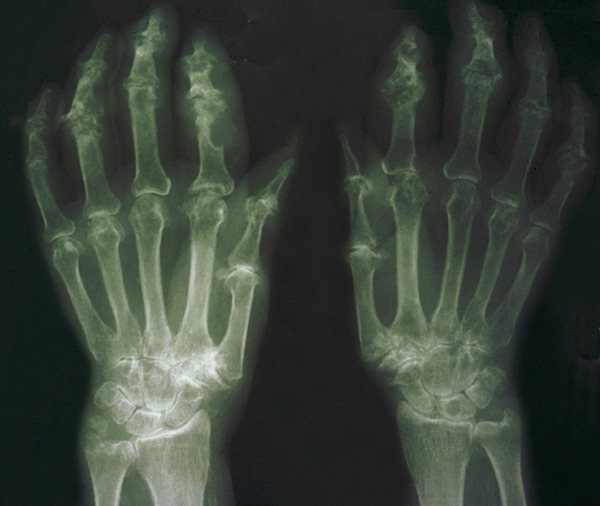

Les radiographies permettent de déceler des modifications ostéocartilagineuses asymétriques (mains, pieds, poignets, coudes, genoux), secondaires à la réaction inflammatoire autour des tophus, comportant :

• des érosions osseuses initiales caractéristiques : encoche épiphysaire (fig. 3) avec un éperon osseux (aspect en hallebarde) ;

• une image d’empreinte dans les parties molles (augmentation de la densité des parties molles dues au tophus) très évocatrice (fig. 4) ;

• un interligne longtemps conservé (contrairement aux autres rhumatismes destructeurs) [fig. 3] jusqu’au stade de goutte chronique et l’absence de raréfaction osseuse périarticulaire permettant de différencier la goutte d’autres arthropathies ; à un stade avancé, la goutte tophacée peut avoir un potentiel destructeur à la fois articulaire et osseux (fig. 4).

La forme pseudorhumatoïde est rare (5 %), simulant une polyarthrite rhumatoïde. L’arthrite chronique à PPC se présente comme une oligo- ou une polyarthrite, avec parfois des signes systémiques d’inflammation (élévation de la vitesse de sédimentation et de la protéine C-réactive [CRP]). La superposition d’accès aigus microcristallins est évocatrice de ce diagnostic. Il s’agit d’un diagnostic différentiel de polyarthrite rhumatoïde du sujet âgé ou de pseudopolyarthrite rhizomélique. Le diagnostic repose sur la mise en évidence des cristaux de PPC, même si les radiographies standard sont évocatrices. L’atteinte radiographique associe des calcifications des cartilages articulaires (fig. 7) et des fibrocartilages (fig. 8, 9, 10 et 11) [à rechercher systématiquement sur les radiographies de poignets, genoux et symphyse pubienne]. La mise en évidence d’une chondrocalcinose sur des radiographies standard renforce le diagnostic de rhumatisme à PPC mais l’absence de dépôts calciques ne l’élimine pas (la sensibilité de la radiographie standard étant imparfaite). L’échographie peut mettre en évidence des dépôts de PPC, qui apparaissent comme une fine bande hyperéchogène au sein des cartilages hyalins et comme des points scintillants dans les fibrocartilages ou dans la membrane synoviale. La sensibilité de l’échographie est bien supérieure à celle de la radiographie standard. Le scanner peut également mettre en évidence des dépôts calciques évocateurs, notamment au niveau du rachis ou du bassin qui sont plus difficilement explorés par les radiographies et l’échographie.